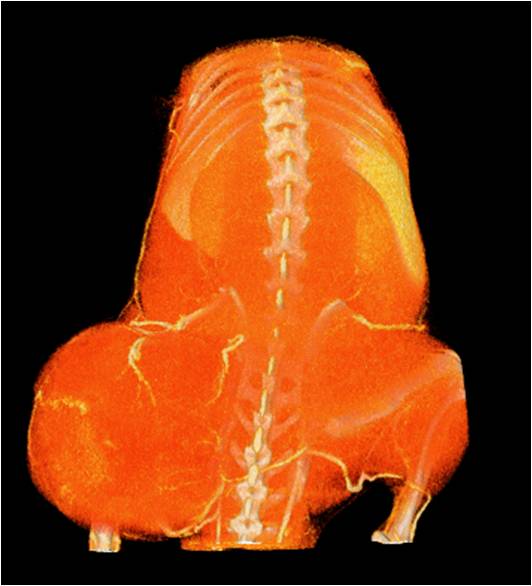

能進(jìn)行全身血管成像研究,獲得高分辨率的血管造影影像;

心血管

胸部和心血管的層析成像 胸部和心血管的3D圖像